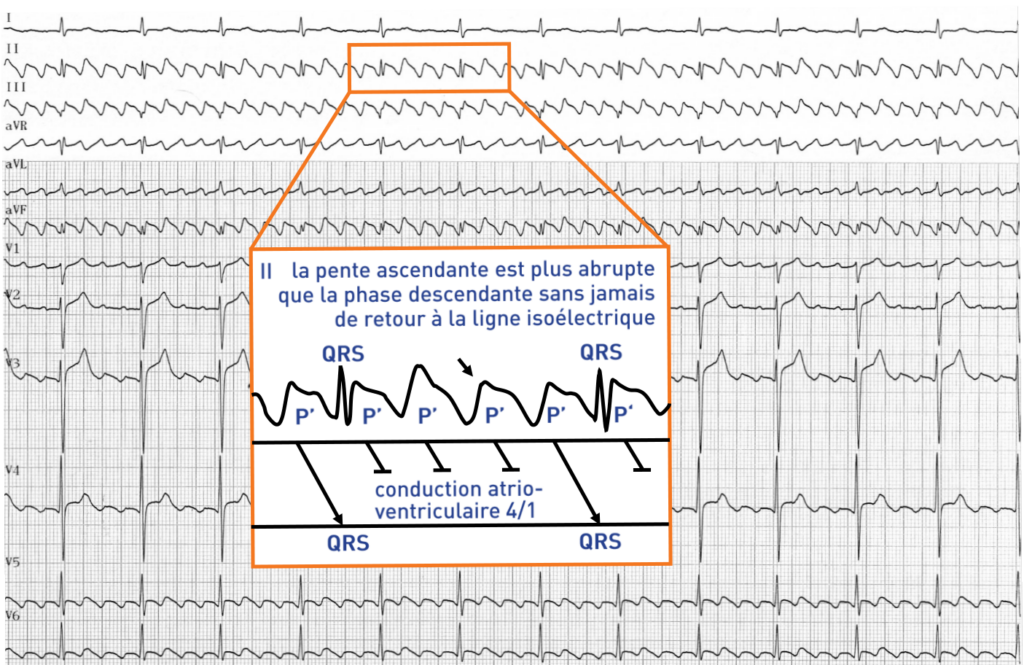

• Dérivations inférieures (DII, DIII, aVF) : on retrouve dans ces dérivations l’aspect typique en dents de scie, en toit d’usine ; les ondes f apparaissent sous l’aspect d’accidents diphasiques avec une négativité prédominante (plus voltée et plus large) suivie d’une positivité plus réduite avec une pente ascendante plus abrupte que la phase descendante sans jamais de retour à la ligne isoélectrique. Un aspect de plateau peut être observé durant la phase descendante.

• La réponse ventriculaire la plus fréquente est de type 2/1 et la constatation d’une tachycardie à 150 bpm doit faire évoquer de principe un flutter atrial. La conduction atrioventriculaire peut être altérée avec un aspect 3/1, 4/1 ou même un aspect de bloc auriculo-ventriculaire complet. Un des tracés suivants illustre le cas où au contraire la conduction est améliorée avec un rapport 1/1. Parfois la conduction est variable. On observe alors une fréquence ventriculaire apparemment irrégulière. L’examen des cycles RR permet toutefois de retrouver des séquences répétitives avec un aspect caractéristique de Wenckebach alterné.